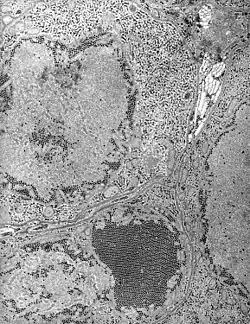

Sección de las gándulas salivares de un mosquito conteniendo las partículas del virus. | ||